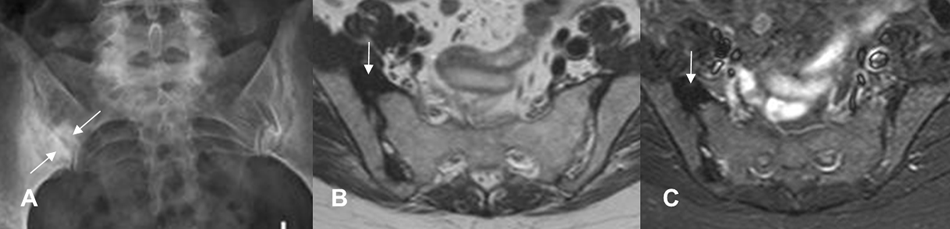

Fig 58 B. Espondilitis anquilosante.

RM coronal en STIR. Lesiones agudas bilaterales, identificadas en el mismo corte.

Fig 58 C. Espondilitis anquilosante.

A y B: RM coronal en STIR. Lesiones agudas bilaterales, en A. Si solo se encontrara la lesión del lado izquierdo, esta tendría que verse en 2 cortes consecutivos, para ser considerada positiva. (Flechas delgadas).

Fig 58 D. Espondilitis anquilosante.

A y B: RM coronal en STIR. Lesión aguda derecha, visualizada en 2 cortes consecutivos.

Fig 58 E. Espondilitis anquilosante.

A: Rx AP. Zona de esclerosis, sobre la sacroiliaca derecha.

B: RM axial en T1 y C: RM axial en STIR. La lesión es hipointensa en ambas secuencias, por fibrosis secundaria a lesión de evolución crónica.